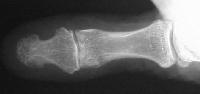

Comparison views of the opposite side:

Click for larger image